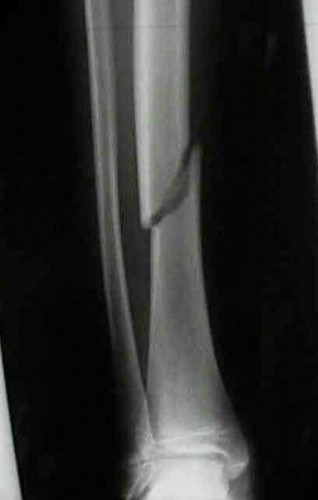

A 3-year-old girl is evaluated for severe, progressive bilateral genu varum. Radiographs demonstrate medial metaphyseal beaking, fragmentation, and depression of the proximal medial tibial physis. According to the Langenskiöld classification of infantile Blount's disease, at which stage does an overt physeal bony bar (epiphyseal-metaphyseal bridge) definitively form across the medial physis, conferring a high risk of recurrence without bar excision?

Options:

- Stage II

- Stage III

- Stage IV

- Stage V

- Stage VI

Correct Answer: Stage VI

Explanation:

The Langenskiöld classification describes progressive radiographic changes in infantile Blount disease. Stage I-IV show worsening metaphyseal beaking and stepping. Stage V shows a deep cleft separating the medial epiphysis into two portions. Stage VI is definitively characterized by the formation of a solid medial physeal bridge (bony bar) between the epiphysis and metaphysis, halting medial growth completely and often requiring bar resection along with osteotomy.